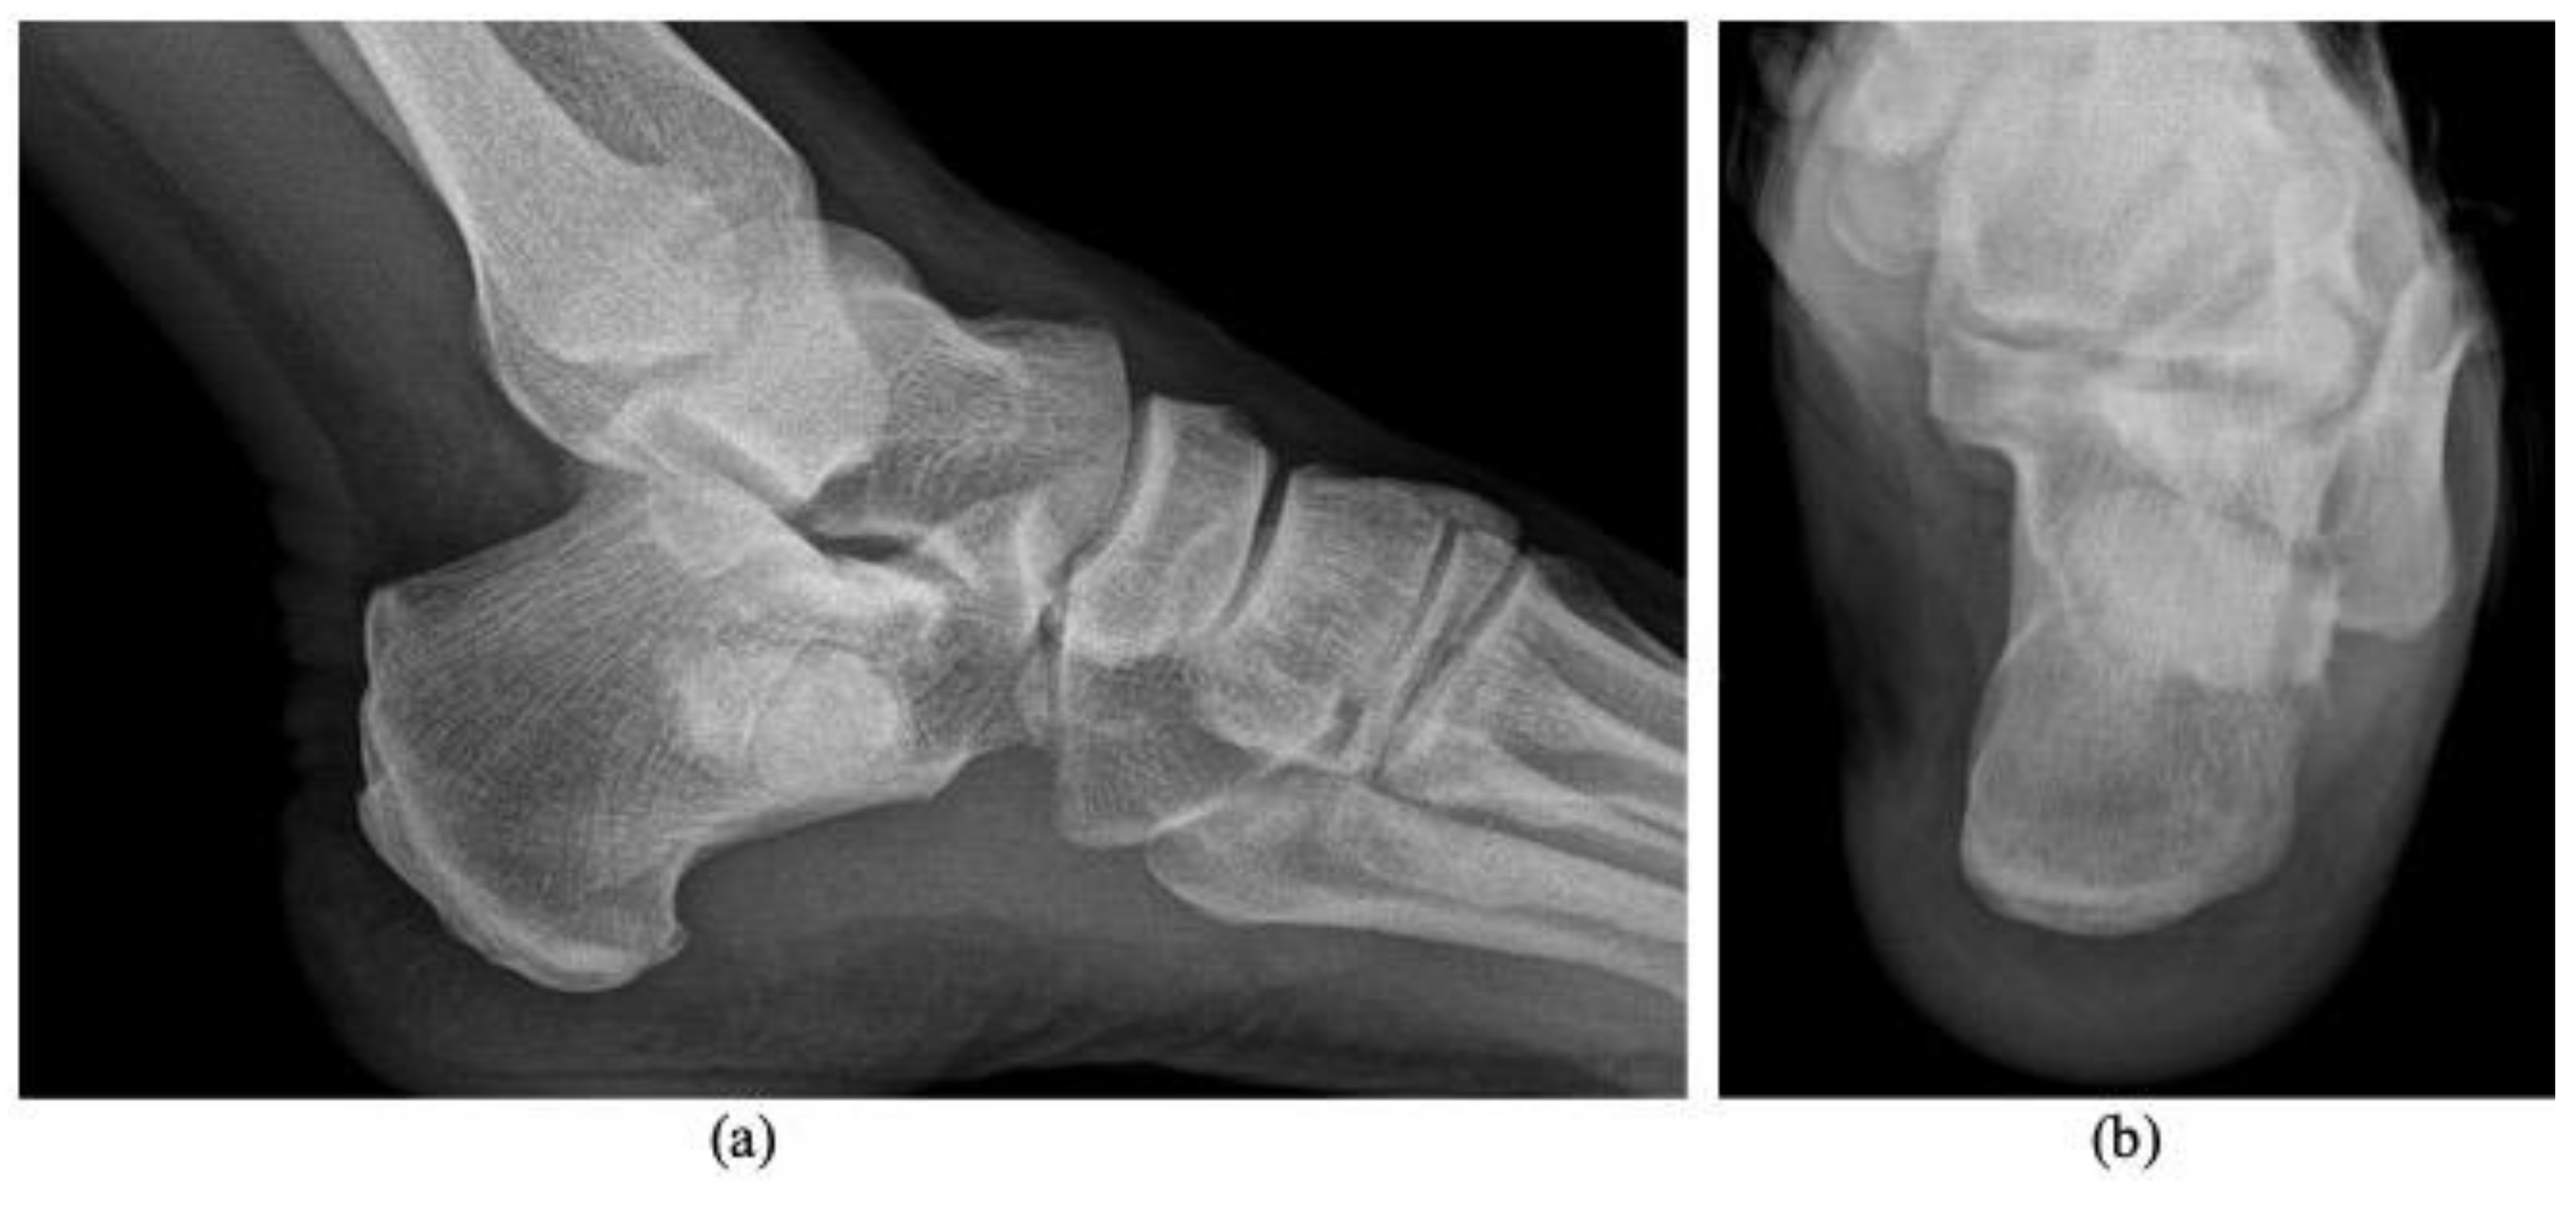

3. Discussion